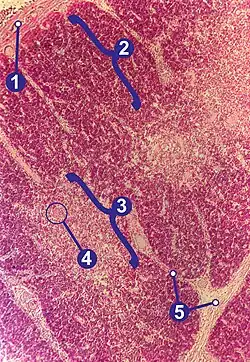

Im Gegensatz zu den übrigen lymphatischen Organen, die ausschließlich aus dem Mesoderm hervorgehen, entwickelt sich der Thymus aus dem Meso-, dem Ento- und dem Ektoderm und wird daher als lymphoepitheliales Organ bezeichnet. Histologisch lassen sich im Thymus Läppchen (Lobuli thymici) mit Rinde und Mark unterscheiden. Besonders im Thymusmark befinden sich beim Menschen und den meisten anderen Wirbeltieren die für das lymphatische Gewebe des Thymus typischen Hassall-Körperchen.